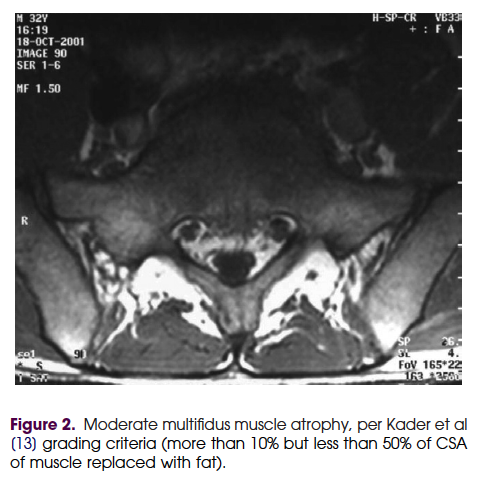

만성요통에서 다열근의 역할에 관한 review논문